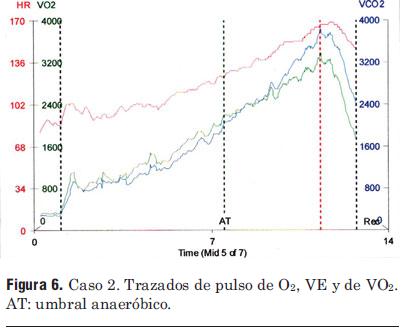

El implante se realizó vía subclavia izquierda. Durante el procedimiento se observó que luego de puncionar la vena y al introducir la guía, la misma no avanzaba libremente; con fluoroscopía se aprecia que la guía avanza reiteradamente hacia la vena yugular izquierda, no pudiéndose dirigir, como se practica habitualmente, hacia la vena cava superior del lado derecho, a pesar de reiterados intentos. Se procedió entonces a realizar venografía (figura 4), encontrándose la presencia de una vena cava superior izquierda sin comunicación con el lado derecho, la que drena en un seno coronario muy dilatado desembocando en la aurícula derecha. Definida la anatomía y utilizando introductor 11 Fr tipo peel away se coloca catéter electrodo de fijación pasiva, con dos electrodos en su extremo para estimulación (bipolar) y con dos bobinas para desfibrilación (Linox TD 75/16 Biotronik®). Retirado el introductor y utilizando guías apropiadas, a las cuales se preforma con curvas adecuadas que faciliten acceder al ventrículo derecho, se maniobra el catéter con movimientos de avance, retroceso y rotación hasta lograr introducirlo en el mismo. Una vez allí y utilizando otra guía con una curva apropiada preformada se maniobra hasta lograr posicionar los electrodos distales a nivel del ápex del ventrículo derecho (figuras 5 y 6). El umbral de estimulación fue de 0,1 mV a 0,5 ms de ancho de pulso y la onda R medida de 16 mV. Se procede posteriormente a la fijación del electrodo de la forma habitual y a conectar e implantar el cardiodesfibrilador (Lexos VR, Biotronik®) en bolsillo prepectoral. Para finalizar se realiza test de desfibrilación: inducción de fibrilación ventricular mediante choque sobre T, que es correctamente sensada e interrumpida por el dispositivo con choque de 20 J. Tiempo del procedimiento 65 minutos; tiempo de fluoroscopía 7 minutos. No hubo complicaciones y el paciente fue dado de alta 24 horas después.